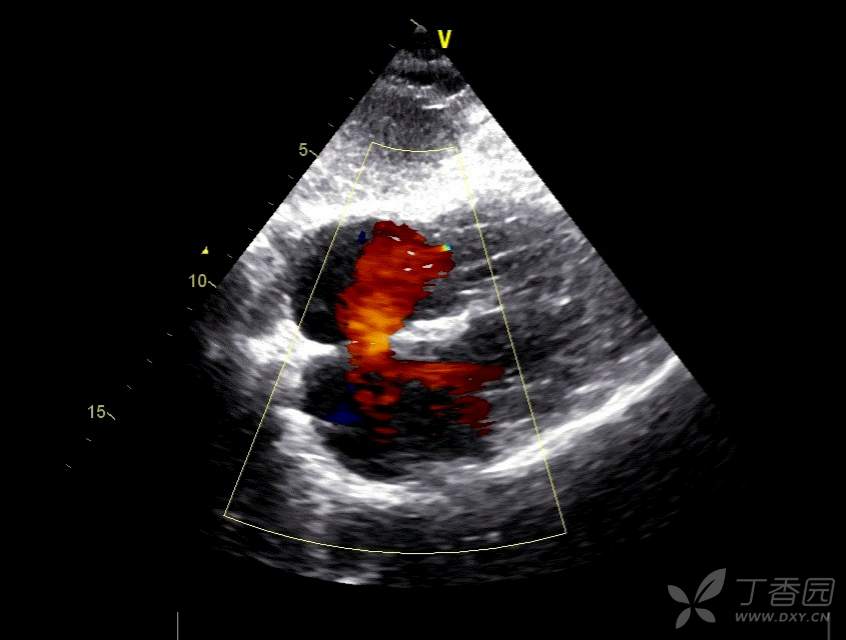

4.大动脉短轴切面:室间隔缺损极佳观察切面(注意室上嵴在此切面的位置),也可以观察房间隔缺损。